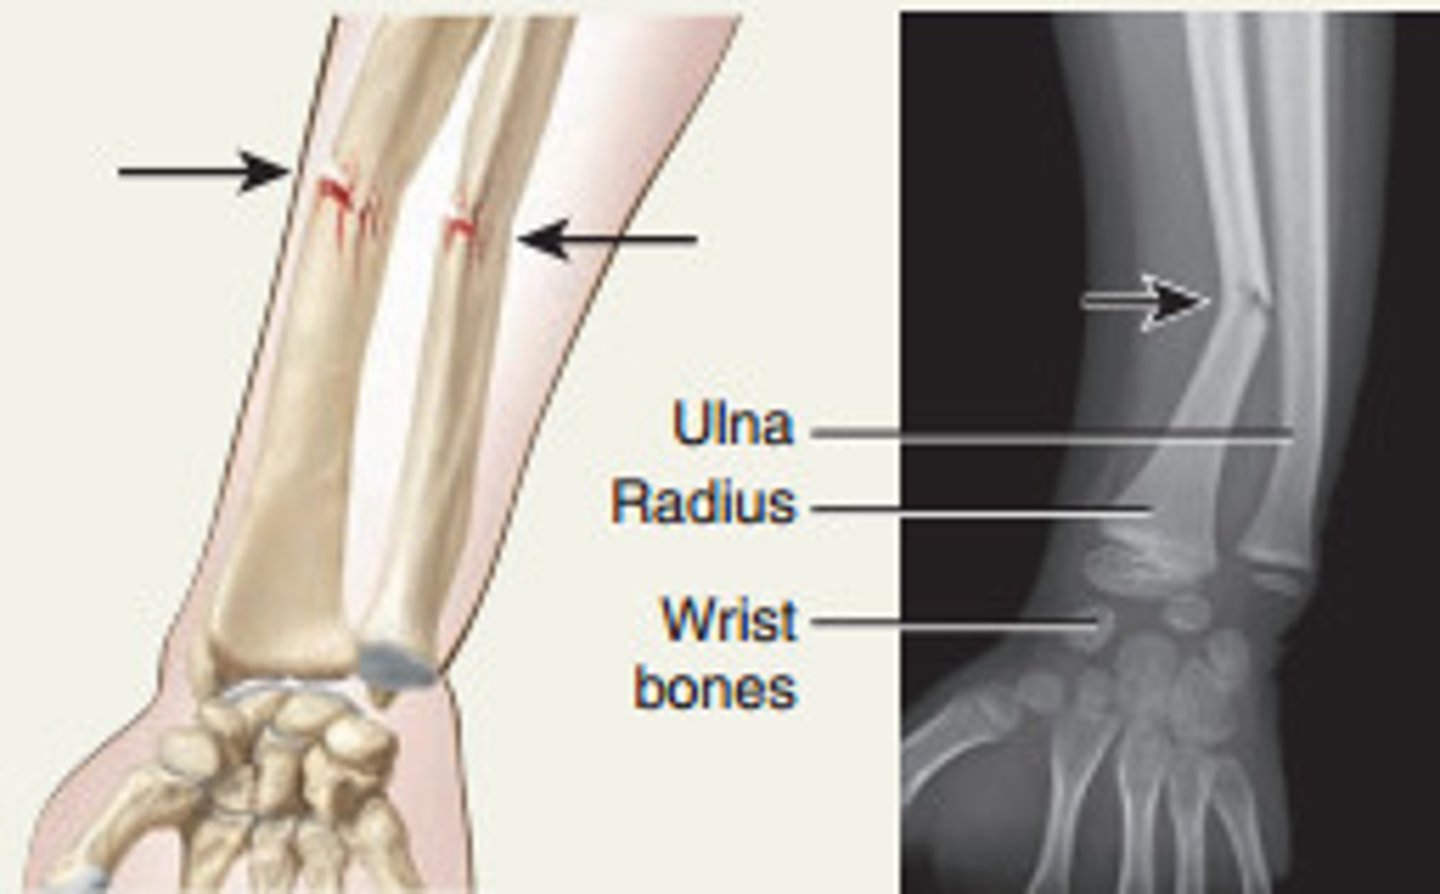

Difference between Colles and Smith fracture

Colles goes backwards (dinner fork)

Smith goes forwards